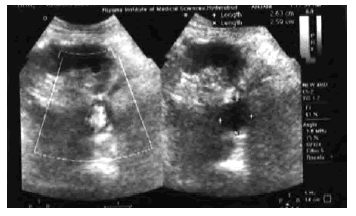

On admission, he was on prednisolone 20 mg/d, mycophenolate mofetil 1.0 g twice daily, and cyclosporine 8 mg/kg/d. The results of his laboratory investigations are reported in Table 1. As the Doppler of renal allograft artery suggested aneurysm (Figure 1), a magnetic resonance angiography was performed. It revealed a saccular aneurysm 2.5 × 2.0 cm with fundus directed inferior of main renal artery of allograft kidney (Figure 2). Upon exploration, the aneurysm was found at the anastomotic site encroaching on the renal hilum. An aneurysmectomy and nephrectomy were done to repair the defect in right internal iliac artery. The results of cultures of his tissue samples from the aneurysm showed Aspergillus flavus, and the nephrectomy specimen showed diffuse cortical necrosis. No fungus was identified in the allograft by use of special stains. He began imipenem and amphotericin B. He was given amphotericin B to a cumulative dosage of 2.7 g. He has been on regular maintenance hemodialysis with us for the past 18 months.

Figure 1. Doppler of Renal Allograft Artery (Patient 2): Anechoic Saccular Out Pouching